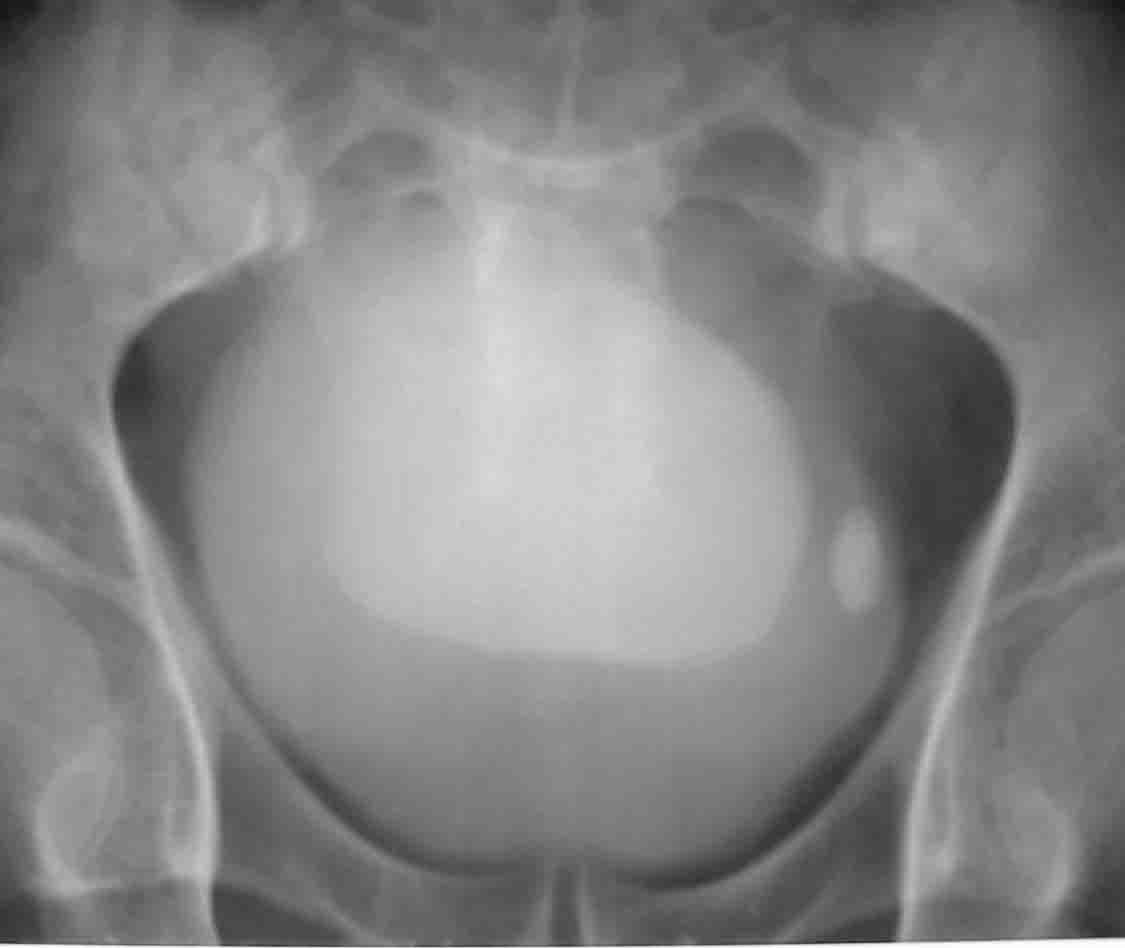

性别:男 60岁,因左侧输尿管末端结石行ivp,上述5张片分别为kub片和7分 15分 30分及120分钟延迟片.

考虑可活动性膀胱结石

膀胱内高密度影应为造影剂充填后改变 考虑囊肿 ,巨大膀胱隙室?, 建议b超 ct检查,加照斜位、侧位或在透视下点片.

随着时间的延长,膀胱内高密度病灶密度逐渐增高,支持膀胱炎并膀胱巨大憩室的诊断.